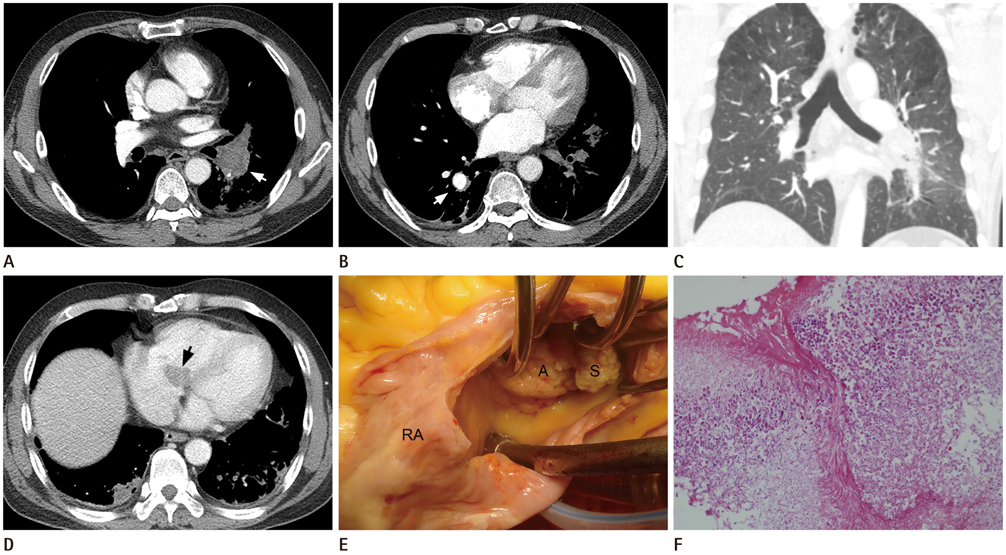

A Mycotic Pulmonary Artery Aneurysm Associated with Candida Endocarditis: Case Report

- We report a case of a mycotic pulmonary aneurysm associated with Candida endocarditis in a 53-year-old male with lymphoma. The initial diagnosis was a pulmonary artery aneurysm attributable to vasculitis, such as that associated with Behcet's disease, but a mycotic pulmonary artery aneurysm was later considered as a differential diagnosis. Identification of valve vegetation on the chest CT was helpful in this regard. We review the literature on the disease etiology, radiological findings, and management options.